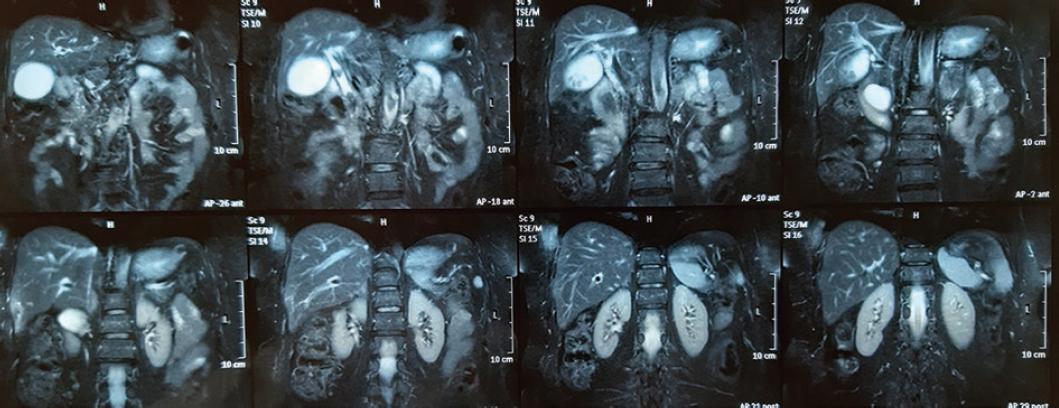

Como parte del protocolo diagnóstico se solicitan resonancia magnética (RM) y colangio-RM, que identifican un divertículo duodenal descrito como una cavidad de pared delgada, en la pared medial de la segunda porción del duodeno, además de coledocolitiasis y litiasis vesicular (Fig. 1). En la reconstrucción de la colangiografía se aprecia un divertículo de aproximadamente 3 cm que comprime la vía biliar, además de dilatación de la vía biliar de hasta 23 mm, con dos litos (uno en el tercio inferior del colédoco y otro por debajo de la carina) (Fig. 2).

Figura 1 Resonancia magnética en la que se observan cálculos biliares, colelitiasis, imagen quística en la cabeza del páncreas y dilatación de la vía biliar.